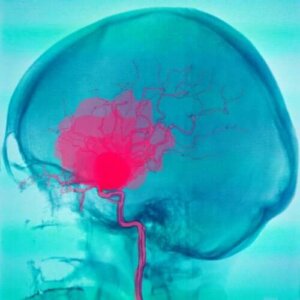

الجافية والعنكبوتية اثنان من أغشية الدماغ الثلاثة التي يمتلكها البشر. والأغشية الدماغية هي الهياكل التي تبطن الجهاز العصبي المركزي. ويشير نزف تحت العنكبوتية والورم الدموي تحت الجافية إلى نوعين من النزف الدموي الذي يحدث في هذين الغشاءين الدماغيين.

في حالتي نزف تحت العنكبوتية والورم الدموي تحت الجافية، أول ما يحدث هو تدفق الدم خارج الأوعية الدموية، والتي توجد في الحيز بين الأغشية، وهو ما يتلق أنسجة الدماغ.

يظهر نزف تحت العنكبوتية عندما يتجمع الدم بين العنكبوتية والأم الحنون. يأتي الدم عادةً من الشرايين لأسباب عديدة مختلفة. أكثر هذه الأسباب شيوعًا هو تمزق تضخم وعائي.